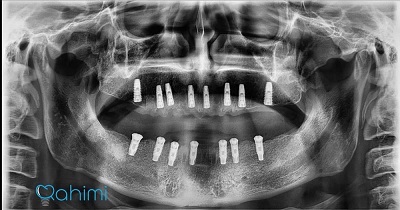

دکتر حامد رحیمی متولد سال ۱۳۶۷ می باشند.ایشان در سال ۱۳۸۵ موفق به ورود به رشته دندانپزشکی دانشگاه علوم پزشکی تهران شدند و در سال ۱۳۹۱ فارغ التحصیل گردیدند.در سال ۱۳۹۴ پس از گذراندن طرح دوره دکتری عمومی در استان قم موفق به قبولی در رشته جراحی لثه و ایمپلنت دانشکاه علوم پزشکی تهران گردیدند.ایشان از سال ۱۳۹۷ و پس از کسب بورد تخصصی به عنوان عضو هیات علمی دانشگاه علوم پزشکی قم مشغول هستند.

- ایمپلنت

- پیوند استخوان

- پیوند سینوس

- ایمپلنت فوری

- ایمپلنت دیجیتال

- پیوند لثه

- جراحی لثه

- جراحی افزایش طول تاج

- لیفت لثه

- لیزر

- جراحی و کشیدن دندان